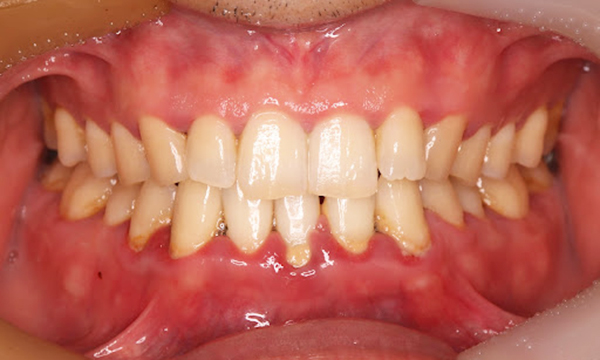

来院2回目、TBI後

症例

SRP後

初診時、TBI前

年齢・性別 27歳・男性

主訴 主訴:左右下の歯ぐきに違和感がある

治療部位:全顎

治療内容 1.歯周基本検査、レントゲン撮影、口腔内写真、歯磨き指導、歯石除去、着色除去

2.SRP(スケーリングルートプレーニング)、再評価

担当者所見 全体的に歯と歯ぐきの境目に歯垢(細菌の塊)が残り、日々のホームケアで落とし切れていなかったことと、歯科医院への定期検診の習慣がなかったことから、全顎的な歯肉炎になってしまったと考えられる。

歯周基本治療とホームケアで歯ぐきの腫れや歯周ポケット、出血率などかなり改善されたが、出血がまだ0%ではない為、引き続き歯ブラシの当て方をお伝えしつつ今後は定期検診で3ヶ月おきに再発しないよう一緒に管理していく。